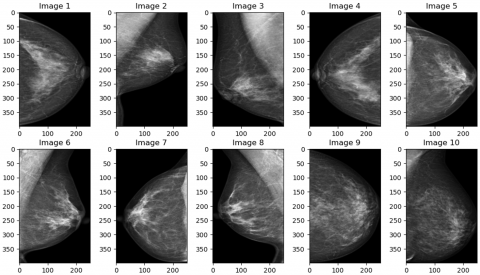

The RSNA screening mammography breast cancer detection dataset is a large dataset specifically designed for developing machine learning models for breast cancer detection. It consists of 54,713 mammographic images from around 11,000 patients, with each patient having at least four images taken from different projection angles and laterality to ensure comprehensive coverage of the breast tissue. The dataset includes crucial metadata such as age, implantation status, BIRADS scores, and breast density, which are important features for classification and risk assessment. The mammograms were originally stored in DICOM format and later resized to 512×512 pixels and converted to 8-bit grayscale to standardize the images for deep learning model training. The example of the images is shown in Figure 1. Figure 1 illustrates a visual comparison between mammogram images representing two distinct classes: the normal class (first row) and the cancer class (second row). In the first row, images depict mammograms from patients classified as normal, meaning no cancerous regions are detected. These images exhibit smooth, uniform breast tissue without any apparent masses or irregularities. The mammograms show clear areas with no signs of abnormal growth or suspicious features. In contrast, the second row contains mammograms from the cancer class, where cancerous regions are present. These images demonstrate noticeable differences compared to the normal class, with visible irregular masses or calcifications that may indicate the presence of malignant tumors. These abnormalities are typically denser and have an uneven shape, which is characteristic of cancerous tissue in mammograms. The visual differences between the normal and cancerous mammograms highlight the importance of feature extraction and detection, as well as the role of the deep learning model in distinguishing between these two classes to support early and accurate diagnosis.

Figure 1. Sample images from the RSNA dataset [21]